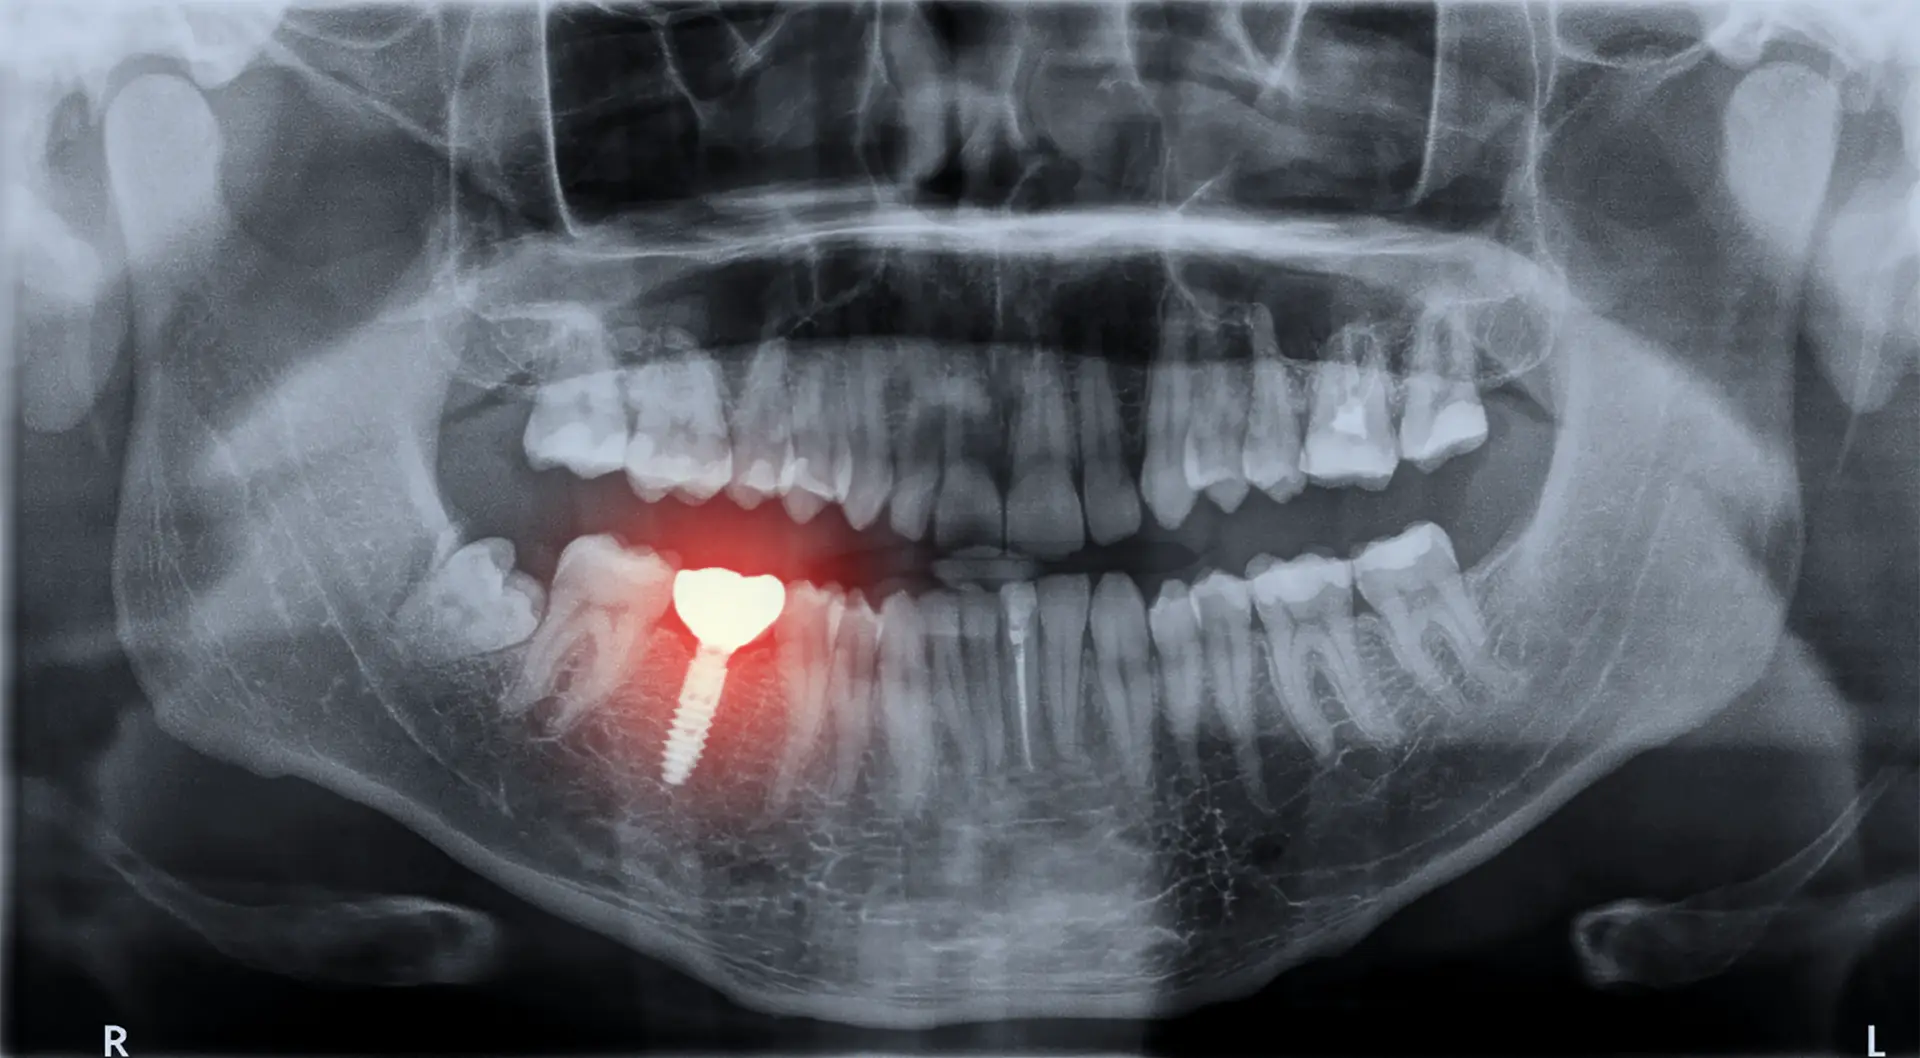

Az utóbbi években a fogászati implantátum egyre több figyelmet kap, hiszen a modern technológiának köszönhetően kiváló megoldást kínál azok számára, akik elvesztették fogaikat. A fogbeültetés egy olyan eljárás, amely során mesterséges foggyökeret ültetnek az állcsontba, majd ehhez rögzítik a műfogat. Az implantátumok természetes megjelenéssel bírnak, és időtálló minőségben szolgálják a teljes fogsor kényelmét.

A beültetési folyamat több lépésből áll. Szükség esetén a szájhigiénia helyreállítása történik meg, az esetleges szuvas fogak tömése, a fogkő eltávolítása.  Az állcsont megfelelő állapotáról szintén fontos meggyőződni, ugyanis ettől függ, hogy a speciális felületi kialakítással rendelkező műgyökér kellően képes-e majd rögzülni abban. Szükség esetén csontpótlásra is lehetőség van, ha a tartós foghiány következtében a csont visszahúzódott volna. Ezt követi egy műtéti eljárás, amely során a mesterséges foggyökeret behelyezik az állcsontba, majd egy gyógyulási időszak következik, amikor a csont összenő az implantátummal, biztosítva annak stabilitását.

Az utókezelés szintén kiemelt szerepet játszik a sikeres beültetésben. A páciensnek rendszeresen ellenőrzésekre kell járnia, hogy az orvos felmérje az implantátum állapotát és szükség esetén beavatkozzon. Fontos a megfelelő szájhigiénia betartása is, hiszen a tisztántartás elengedhetetlen az implantátum hosszú élettartamához.